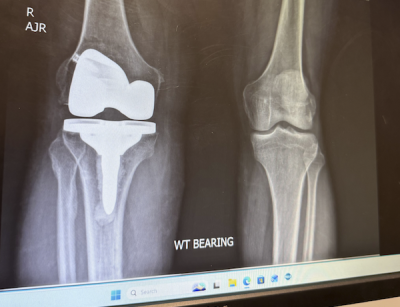

I had a rod extract from my right leg Tibia and my knee replaced. I was playing pickleball nine weeks later. I didn’t think I would be able to do that for at least six months. The surgery went well, and I am on my way to a full recovery.